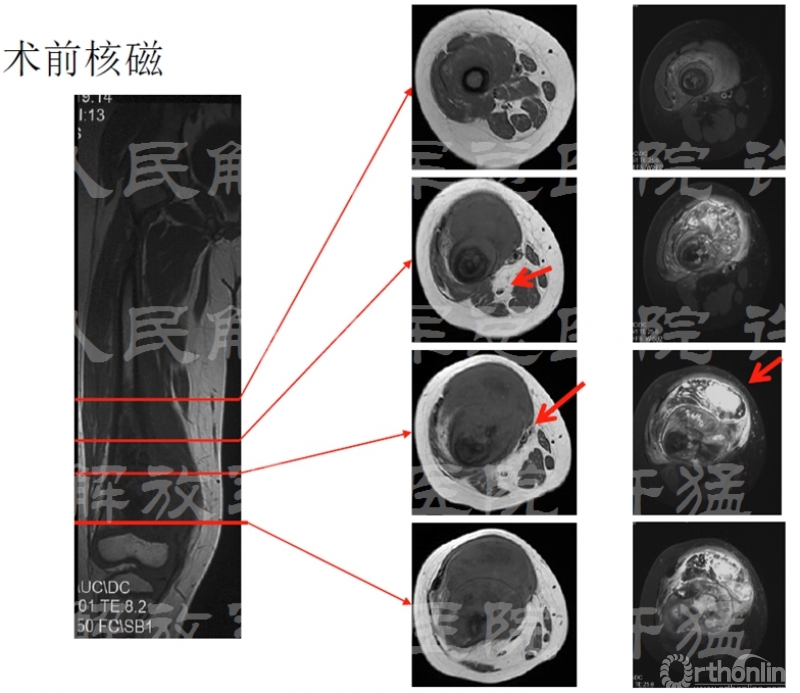

治疗前相关检查:

核磁显示穿刺通道有污染伸膝装置的可能